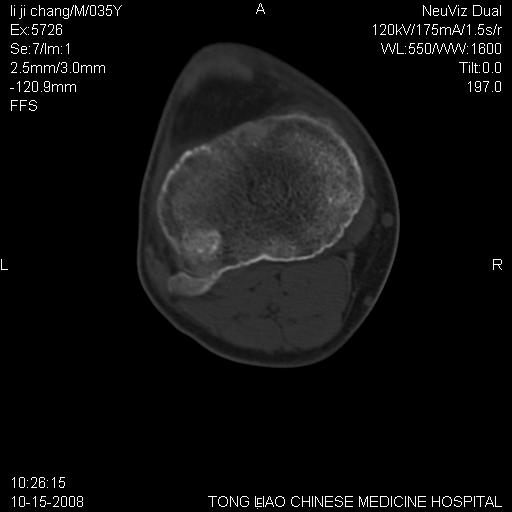

男,35岁,骨科诊断骨性关节炎。继往使用过激素,现股骨头坏死。膝关节病变,请会诊

一元论-----亦考虑为坏死

支持考虑无菌坏死

支持无菌坏死伴退行性骨关节病.

剥脱性骨软骨炎:是一种关节下软骨及软骨下骨缺血性坏死。

支持 无菌性坏死伴退行性骨关节病。

退变本身就可以有囊变.